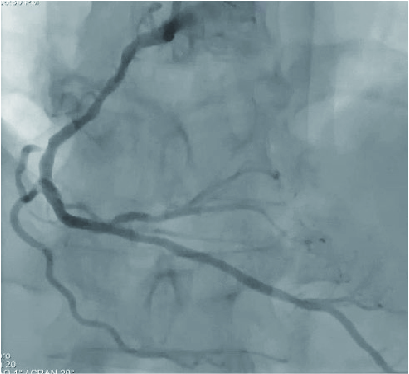

The post-PCI FFR measurement showed a value of 0.93 in the distal RCA (Fig. 1) and the recovery of blood flow (Fig. 2)

RCA was stented with a 2.5 mm × 30 mm DES optimizing with POT-side-POT